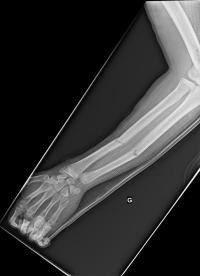

Fracture de l’avant-bras 31 mars 202519 mars 2024 par Damien Traitement Traitement orthopédique Embrochage centro-médullaire